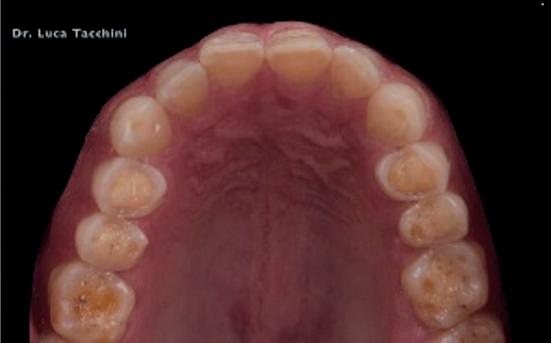

Luca Tacchini, Odt – erosioni da perimolisi

Che i pazienti siano consapevoli di avere un problema o non lo siano, il dentista e l’igienista dentale sono invece sentinelle che non possono esimersi dal saper riconoscere e curare segni e sintomi presenti non soltanto nel cavo orale. Lesioni a carico dei tessuti molli quali afte estese e cheiliti angolari, nella anoressia. Escoriazioni e ipercheratosi dovute a traumi meccanici da induzione al vomito nella bulimia. Spesso per entrambe le patologie con interessamento delle commessure labiali. Danni che interessano anche i tessuti duri, quali erosioni provocate da alimenti fortemente acidi o perimolisi da reflusso di fluidi gastrici. Compromissioni non solo esteti -

che ma anche funzionali, inizialmente con perdita di morfologia dentale. Con il perpetrarsi della malattia, queste possono degenerare fino alla perdita della dimensione verticale. Perfino le mani delle pazienti bulimiche possono portare i segni inequivocabili di autoinduzione al vomito, identificati come “Segni di Russel”. Alterazioni del cavo orale contenibili attraverso consigli di igiene da attuarsi post assunzione di sostanze acide (consumate nell’anoressia per compensazione energetica, in quanto ipercaloriche), o post emesi nella bulimia. Sono prescrivibili, inoltre, dispositivi protettivi e procedure di rimineralizzazione per gli elementi dentali.